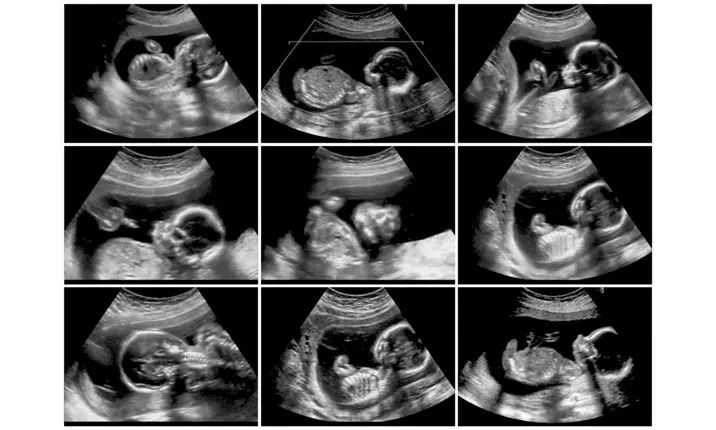

First Trimester Screening

Performed during 11 to 13 weeks of pregnancy

Includes blood tests and ultrasound scan (NT scan)

Helps assess the risk of chromosomal conditions such as Down syndrome

Evaluates certain pregnancy-related markers in maternal blood

Provides early information about fetal health

Second Trimester Screening

Usually performed during 15 to 20 weeks of pregnancy

Includes blood tests often known as triple or quadruple marker screening

Helps assess the risk of chromosomal abnormalities and neural tube defects

Provides additional information about fetal development